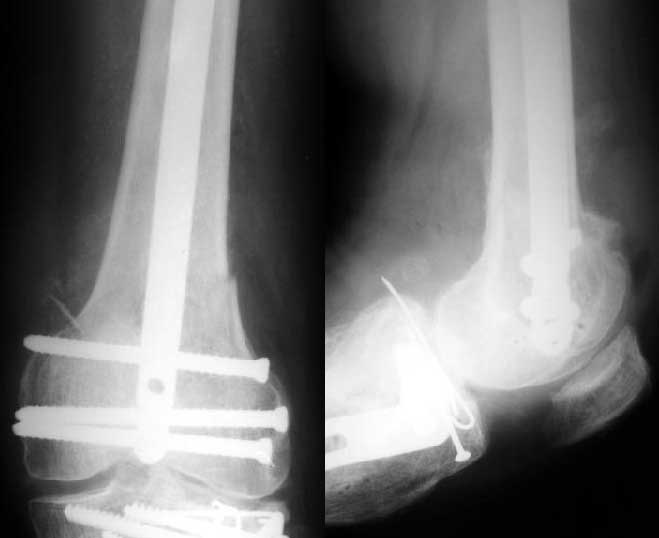

Отправитель: Alexander Chelnokov 27 Декабрь 2003, 21:34

1

Sorry but I've just prepared postop images - attached. A solid 13 mm nail was used. A few degrees of recurvation appears to be which i missed on image intensifier. I'm still uncertain about

advantages/disadvantages of ante/retrograde nailing for such fractures.

Отправитель: V.M.Iyer 27 Декабрь 2003, 21:36

The fixation as you have done is excellent. The locking screws on either side of the # are so apart. When we put in a supracondylar nail thro a keyhole incison in the knee, the locking bolts will be nearer the # and will be more stable allowing him to bear wt early. That was the reason the supracondylar nail was innovated. The locking is done by jig and no freehand method saving time.